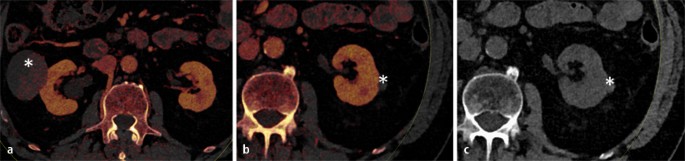

Schnittbildgebung Der Nierentumoren Springerlink